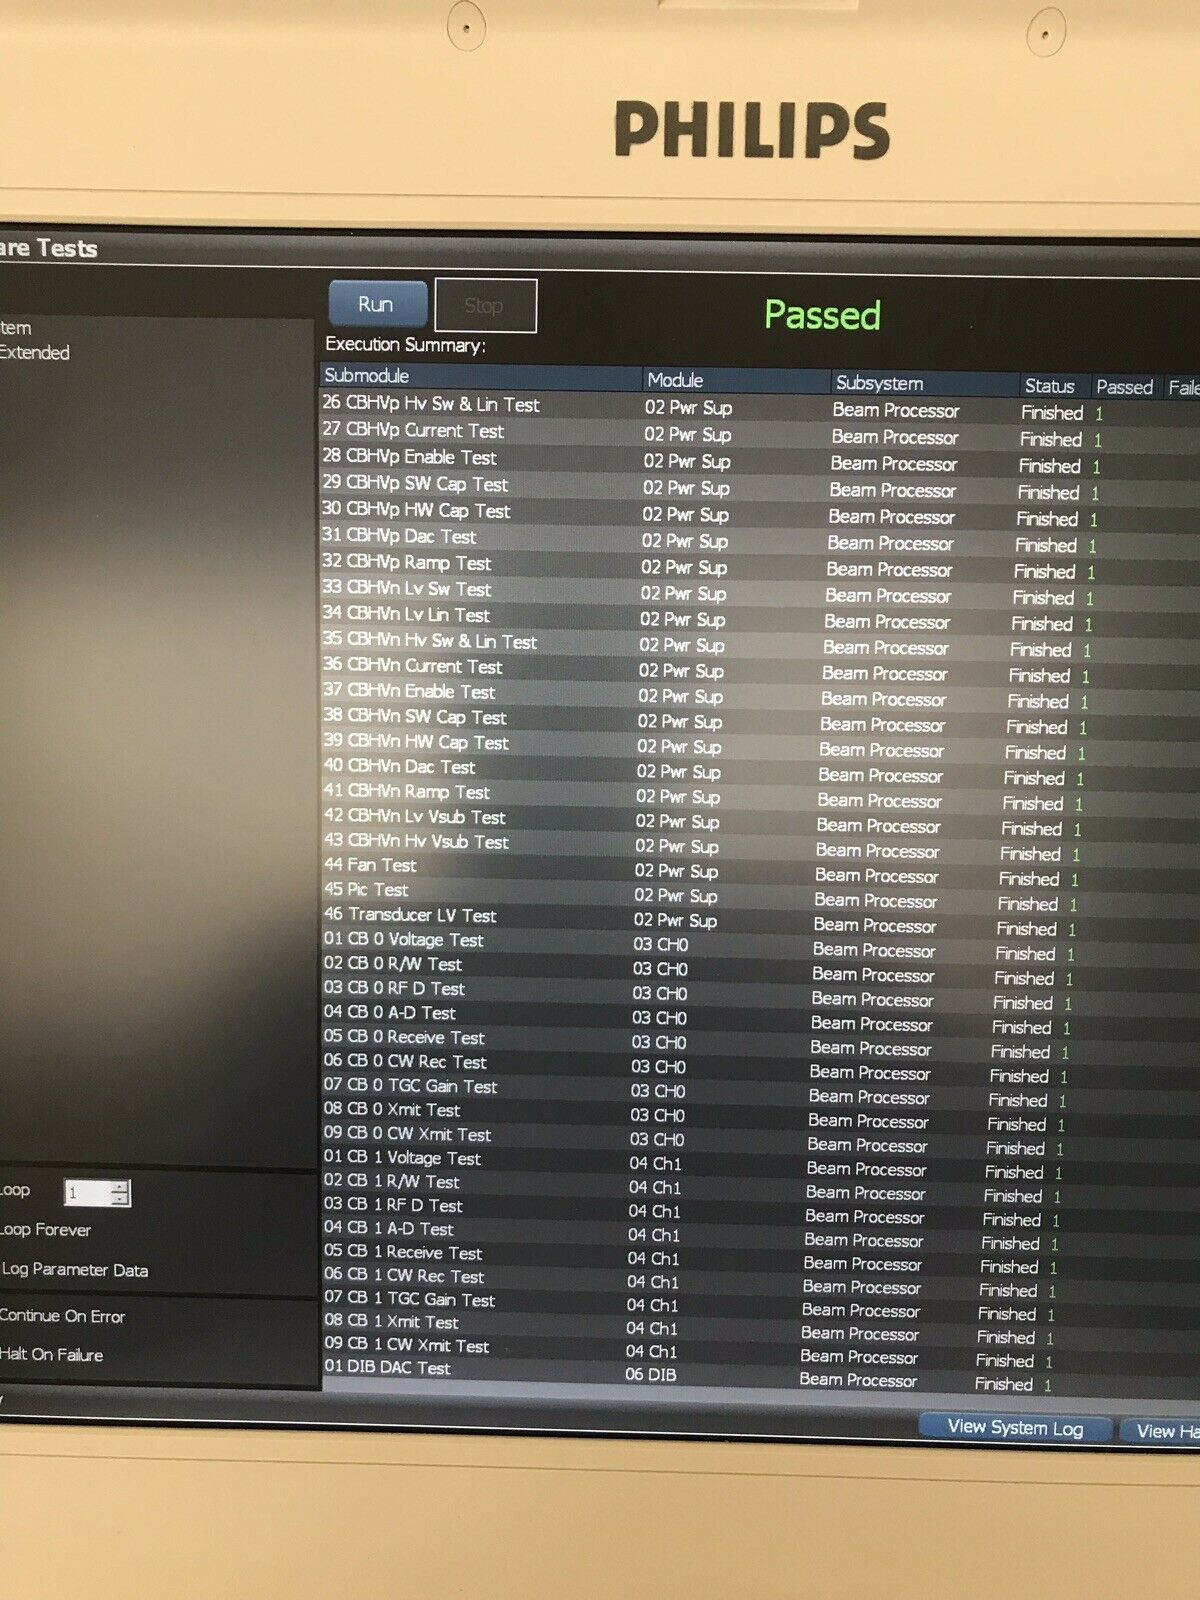

The Philips CX50 2013 Rev 4 Portable Ultrasound System with three probes is a high-performance imaging solution designed for flexibility across a range of clinical applications. This compact, portable ultrasound machine delivers premium imaging quality, making it ideal for point-of-care, cardiology, vascular, and emergency medicine. Equipped with Philips’ advanced imaging technologies like PureWave crystal technology, the CX50 provides exceptional resolution and detail, even in difficult-to-image patients.